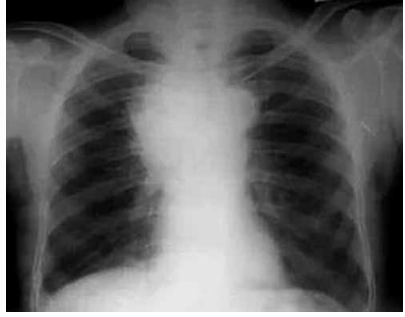

Observe a imagem a seguir:

A imagem mostra um exame de tomografia de tórax que demonstra espessamento pleural > 1,0 cm, difuso, irregular e que se estende à pleural mediastinal, com envolvimento do plano cissural e com redução de volume do hemitórax comprometido.

O quadro é fortemente sugestivo de